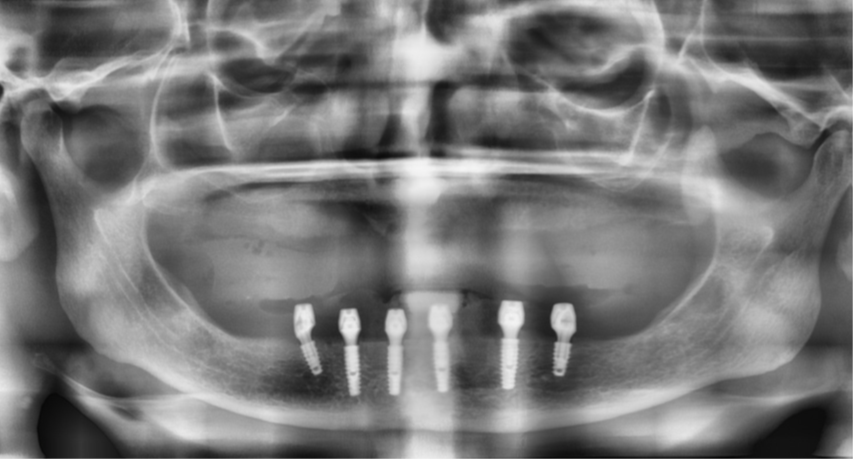

Figura 3 – Raio-X panorâmico inicial sem próteses removíveis em boca.